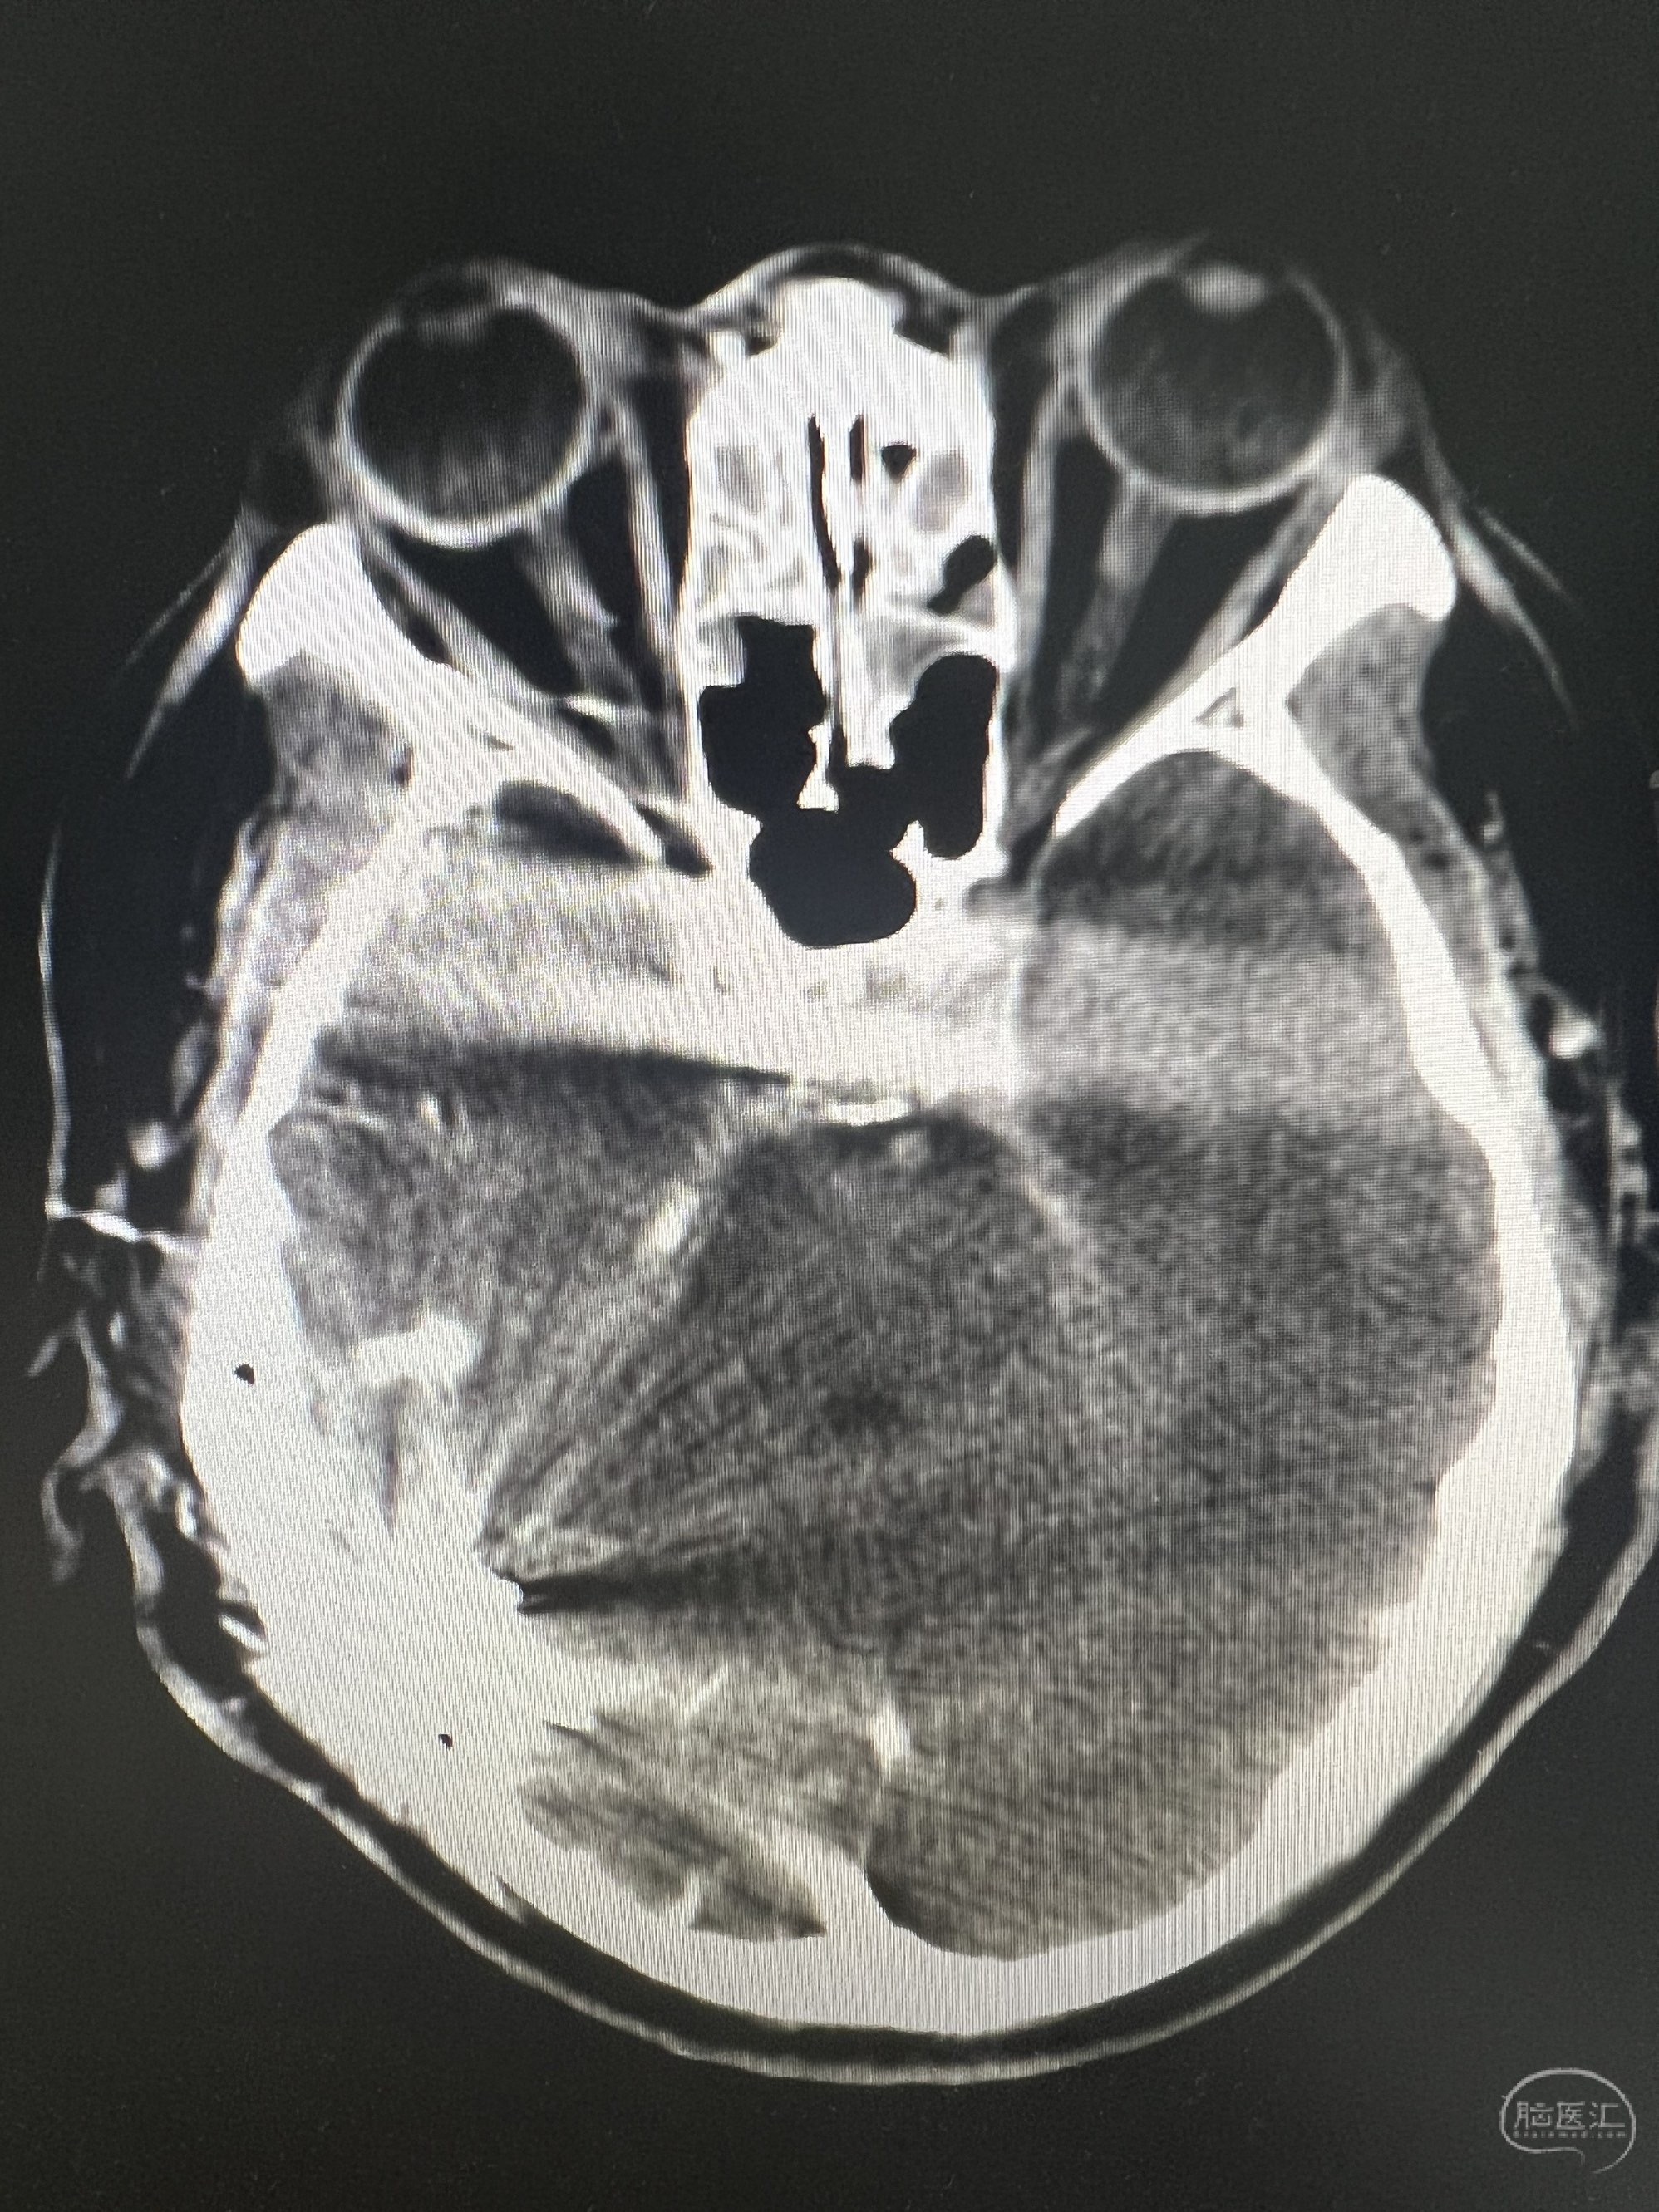

ZXX,M56Y,sah,头颅CTA未见明确动脉瘤。DSA示右侧侧窦区DAVF。